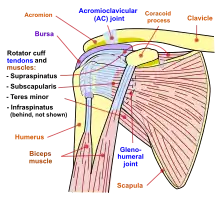

Pectoral girdle—front Diagram of the human shoulder joint, front view

Diagram of the human shoulder joint, front view Diagram of the human shoulder joint, back view